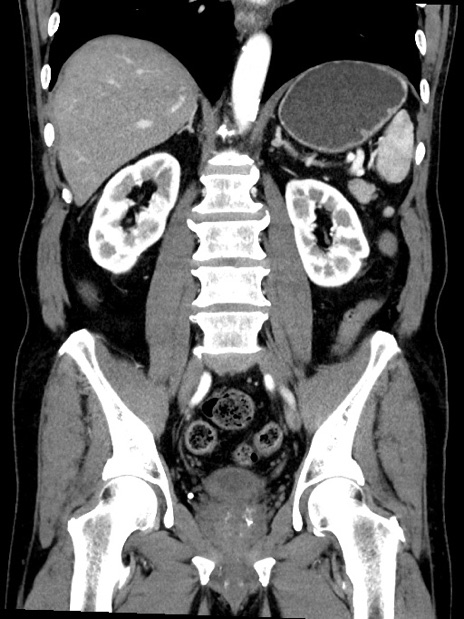

症例35(冠状断像)

【症例】70歳代 男性

【主訴】腹部膨満、嘔吐

【現病歴】昨日より腹部膨満感出現。本日増悪し、仙痛出現。嘔吐あり、受診。

【既往歴】糖尿病、胆摘後

【身体所見】BP 149/80mmHg、HR 74/min、BT 35.9℃、腹部:膨満、軟、圧痛なし。腸雑音減弱あり。上腹部正中切開瘢痕あり。

【データ】WBC 13500、CRP 1.72